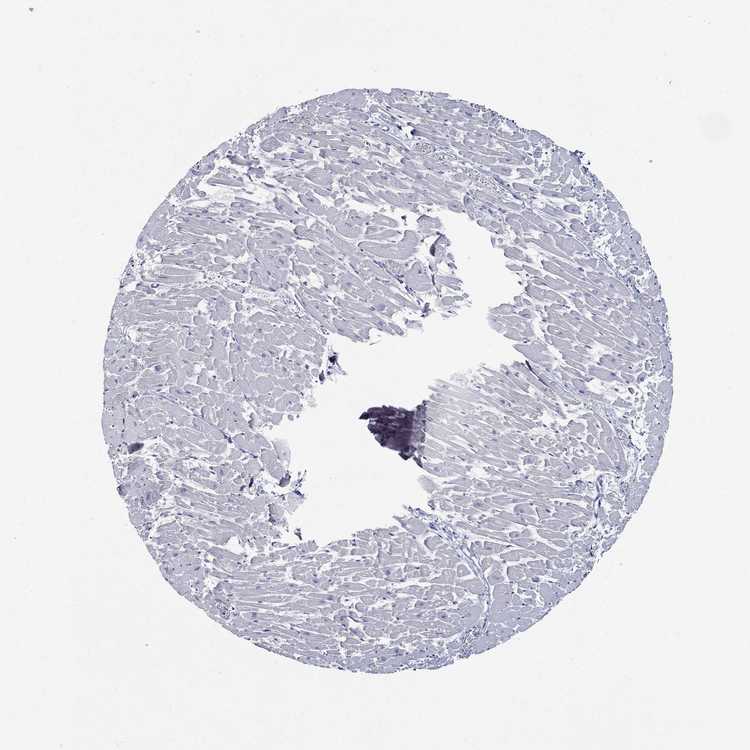

HEART MUSCLE - Antibody stainingi

Antibody staining in the annotated cell types in the current human tissue is reported as not detected, low, medium, or high, based on conventional immunohistochemistry profiling in selected tissues. This score is based on the combination of the staining intensity and fraction of stained cells.

Each image is clickable and will lead to virtual microscopy that enables deeper exploration of all samples and also displays staining intensity scores, fraction scores and subcellular localization as well as patient and tissue information for each sample.

Antibody HPA001868

Cardiomyocytes Not detected